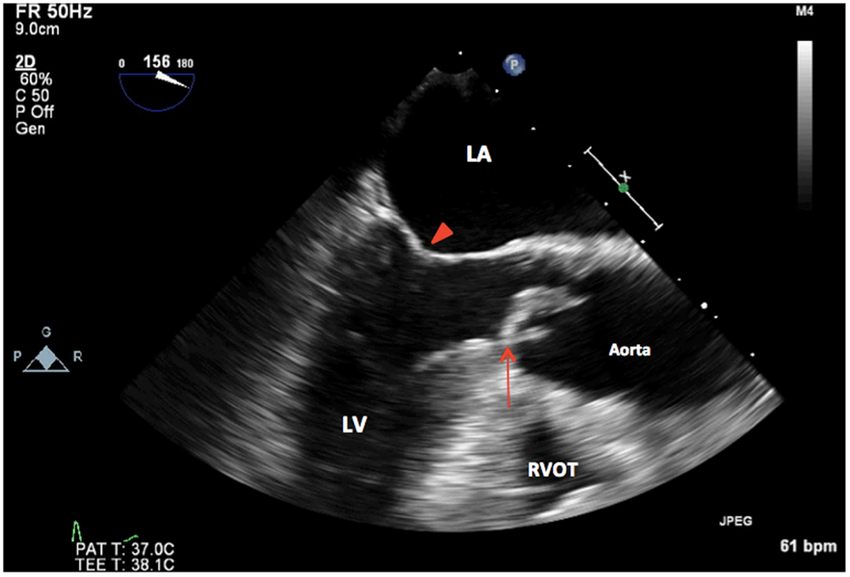

Mid Esophageal 5C

ME 5C 0 degree

Firt view that we get on TEE

Mid esophageal 5 chamber View

0 degree